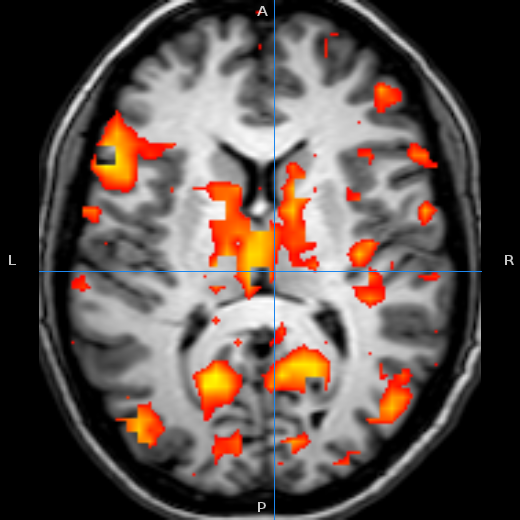

在R中,假设您希望在医学成像中提供像图像背景一样的统计数据。

image函数可以这样做,只需设置第二组颜色的透明性,并使用add=TRUE覆盖它。任何缺失的值都将是完全透明的,并且您可以为其他颜色设置alpha级别(当然,您的图形设备必须支持部分透明性才能工作)。下面是一个简单的例子:

image(A, col=grey( seq(0,1,length.out=12) ) ) # initial plot

hc <- sub('FF$','77',heat.colors(12)) # convert heat colors to have an alpha

image(B, add=TRUE, col=hc) # overlay the new plothttps://stackoverflow.com/questions/10318868